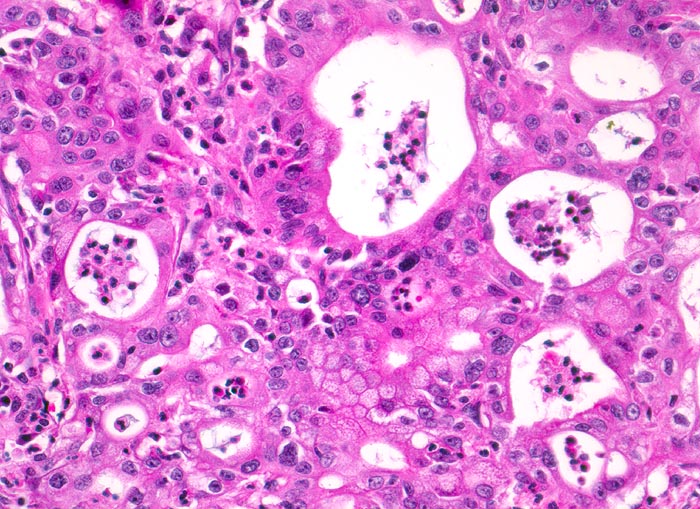

AP/ Duktales Adenokarzinom des Pankreas

Duktales Adenokarzinom des Pankreas

Die meisten Pankreaskarzinome sind mässig bis hoch differenziert und führen zu einer deutlichen desmoplastischen Stromareaktion (derbe Konsistenz). Hochdifferenzierte Tumoren (> 1502) können sehr ähnlich aussehen wie eine chronische Pankreatitis (> 4243). Im Gegensatz zur Pankreatitis sind die neoplastischen Drüsen verformt oder rupturiert und zeigen zelluläre Atypien (grosse polymorphe Kerne mit prominenten Nucleolen). Die Tumordrüsen sind unregelmässig im Stroma angeordnet und nicht lobulär wie in der Pankreatitis. Nicht selten ist eine Nervenscheideninvasion nachweisbar (> 5884). Gelegentlich zeigen die Gänge im tumorfreien Parenchym dysplastische Veränderungen oder der Tumor breitet sich intraduktal entlang des Pankreasganges aus.

• Unregelmässige Anordnung der Drüsen (keine Läppchenarchitektur erkennbar).

• Kribriforme Drüsenformationen.

• Inkomplette Drüsen mit unvollständigen Lumina und Infiltration des Stromas durch Tumoreinzelzellen.

• Nekrotische Tumorzellen in den Drüsenlumina.

• Ausgeprägte Polymorphie und Hyperchromasie der Tumorzellkerne.

• Desmoplastisches Stroma.